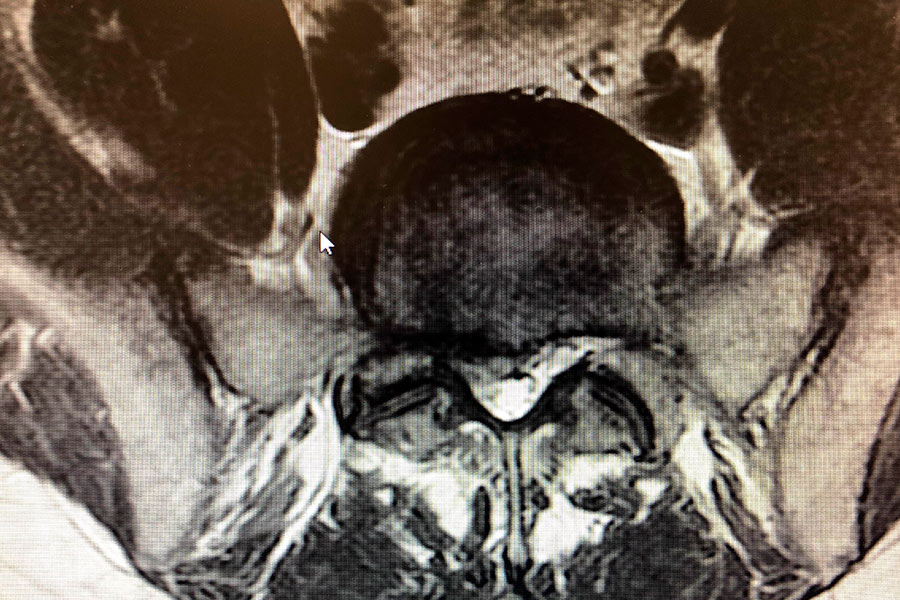

El diagnóstico, desarrollado tras realizar todas las pruebas pertinentes, es de una hernia de pequeño discal L5S1 de pequeño tamaño, situada justamente en la salida de la raíz nerviosa, por lo que hace que el dolor y la pérdida parcial de movimiento sean más acentuados.

hernia-discal-lateralizada